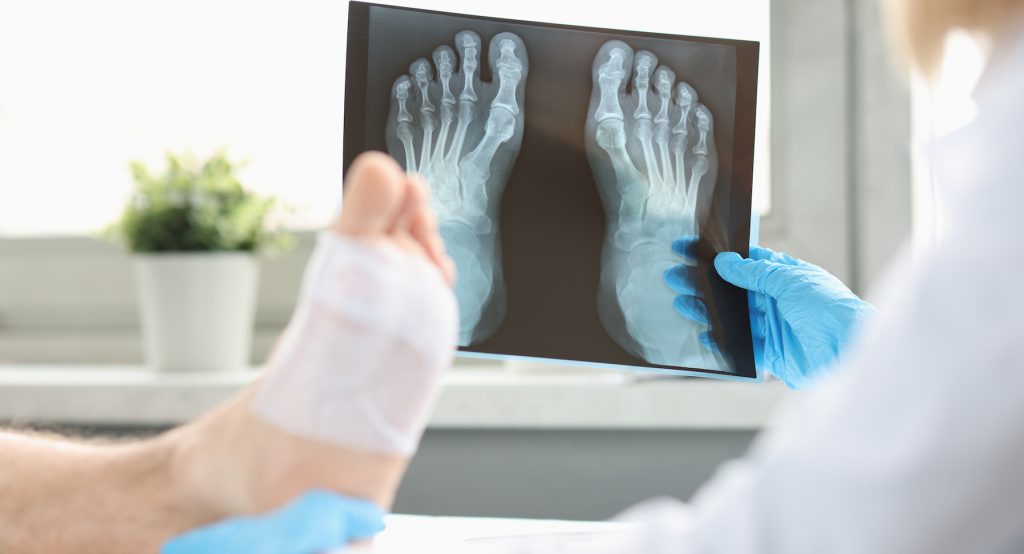

At Canyon Foot and Ankle, Dr. Levi Berry provides expert treatment for foot and ankle fractures and trauma, helping patients find fast relief from pain, swelling, and limited mobility. Fractures and traumatic injuries can occur from sports, accidents, or everyday activities, often leading to significant discomfort and difficulty walking. Left untreated, these injuries can worsen, causing improper healing or long-term complications that interfere with daily life. Serving the Spanish Fork, Utah community and surrounding areas, Dr. Berry uses proven techniques and advanced care methods to stabilize injuries, promote proper healing, and restore strength so patients can return to their normal activities safely and effectively.

Dr. Levi Berry is committed to providing personalized care for patients of all ages dealing with foot and ankle fractures or traumatic injuries in Spanish Fork, Utah. Whether caused by sports accidents, falls, or sudden impacts, fractures and trauma can be both painful and debilitating. At Canyon Foot and Ankle, patients receive a thorough evaluation, customized treatment, and guidance throughout the recovery process to ensure proper healing and reduce the risk of long-term complications. With a focus on restoring strength and mobility, Dr. Berry ensures that each patient leaves not only on the path to recovery but also with the knowledge and support needed to protect their foot and ankle health moving forward. Schedule your appointment today and take the first step toward lasting healing.